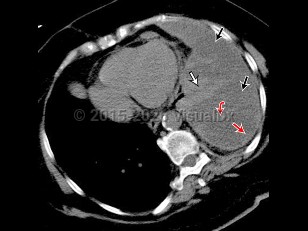

Exudative effusions are due to inflammation from infection or noninfectious etiologies, injury, malignancy, and impaired lymphatic drainage. The primary method of distinguishing transudate from exudate is Light's criteria:

- Pleural fluid protein to serum protein ratio >0.5, or

- Pleural fluid lactate dehydrogenase (LDH) to serum LDH ratio >0.6, or

- Pleural fluid LDH >2/3 upper limit of laboratories' normal LDH